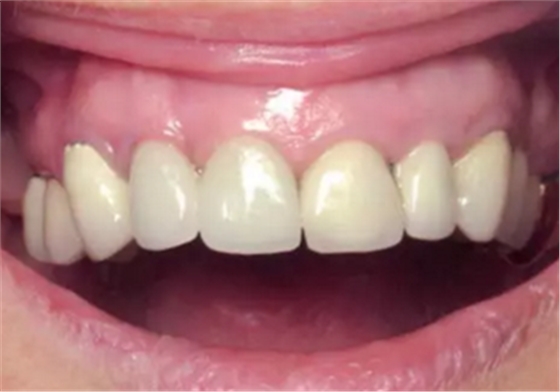

另外,SLA表面可以吸附血漿中的蛋白質(zhì),,并促進(jìn)纖維網(wǎng)狀結(jié)構(gòu)的形成從而加速骨成熟。這對(duì)于拔牙后即刻種植并即刻改善美觀(guān)的治療方式來(lái)說(shuō)是一個(gè)巨大的優(yōu)點(diǎn)。術(shù)后10天(圖21)和4周(圖22)復(fù)查,明確牙齦恢復(fù)狀態(tài)和種植體結(jié)合情況。術(shù)后沒(méi)有出現(xiàn)疼痛、水腫或血腫的情況。

圖21

圖22

結(jié)果

即刻種植即刻負(fù)載在控制良好的情況下也能獲得良好的預(yù)期效果。數(shù)字化拔牙結(jié)合術(shù)前制作螺絲固位的CAD/CAM臨時(shí)修復(fù)可以在不需椅旁粘接的情況下成功實(shí)現(xiàn)即刻負(fù)載。整個(gè)治療流程全部是數(shù)字化的。只需單獨(dú)的手術(shù)過(guò)程就可以實(shí)現(xiàn)個(gè)性化的修復(fù)重建過(guò)程。